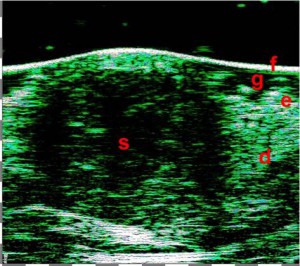

-Υπέρηχος Υψηλής Συχνότητας (HFUS) και Ιστολογία

Εφαρμογές δερματολογίας

-Κύριες παθολογικές διεργασίες